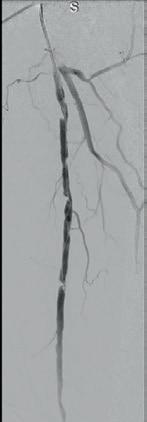

Post-intervention arteriogram

An excellent technical result was achieved. The SFA was widely patent with no significant residual stenosis. The posterior tibial and peroneal arteries were widely patent with brisk flow and no residual stenosis. Significantly improved flow was identified to the foot (Figure 4).

Post-intervention follow-up

The patient had an uneventful postoperative recovery. His post-intervention lower extremity arterial studies demonstrated a significant improvement in both the ABI and toe-brachial index (TBI). At his onemonth postoperative visit, he had completely healed the toe ulcer without any further intervention (Figure 5).